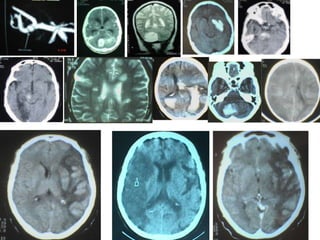

Hemorragia cerebral IntraparenquimatosaCefaleaAlteracion de la concienciaVomitoCrisis epilepticasDiagnostico: TAC de craneo simple

Hemorragia cerebral IntraparenquimatosaSitio : putaminal, nucleo caudado , talamo,lobar, cerebelosa y  puente.Etiologia : HTA,malformacion AV, angioma cavernoso y angiopatiaamiloide, drogas ( cocaina,heroína, fenilpropanolamina) anticoagulantes , tromboliticosMas de la mitad de pacientes, muere o queda con secuelas severas

Hemorragia cerebral IntraparenquimatosaCefaleaAlteracionde la concienciaVomitoCrisis epilepticasDiagnostico: TAC de craneo simple

Hemorragia cerebral IntraparenquimatosaSitio: putaminal, nucleo caudado , talamo,lobar, cerebelosa y puente.Etiologia : HTA,malformacion AV, angioma cavernoso y angiopatiaamiloide, drogas ( cocaina,heroína, fenilpropanolamina) anticoagulantes , tromboliticosMas de la mitad de pacientes, muere o queda con secuelas severas